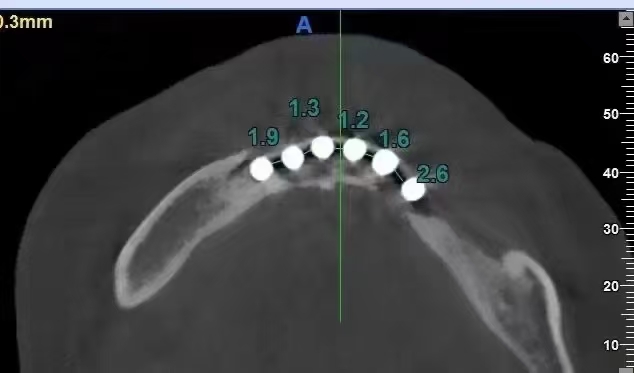

严重的种植并发症一例

严重的种植并发症

触目惊心